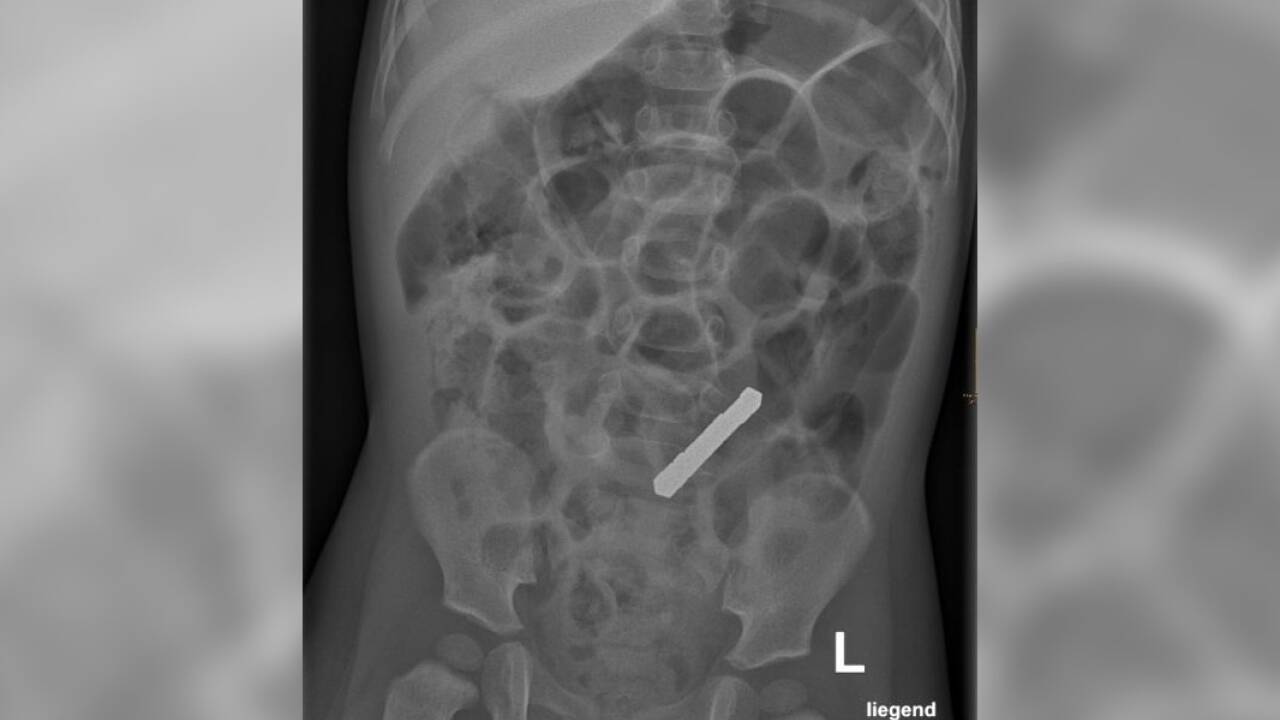

Ein 21 Monate alter Bub spielte mit kleinen, haftstarken Magneten. Das Röntgen ergab: Er hatte zehn geschluckt, die sich im Darm zusammenklammerten.

Die Magneten klammerten sich durch die Darmwände zusammen.